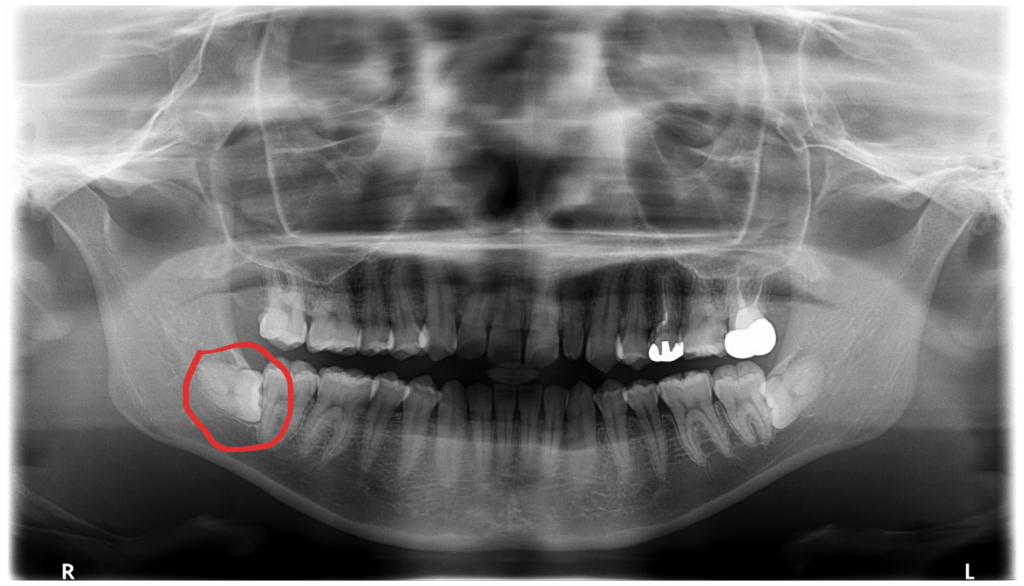

右下6番の痛み・歯ぐきの腫れで来院された方の治療(根管治療)【保険診療】

「右下の奥歯が痛い」「歯ぐきが腫れている」という症状でご来院された患者さんの治療内容をご紹介します。 初診時、右…